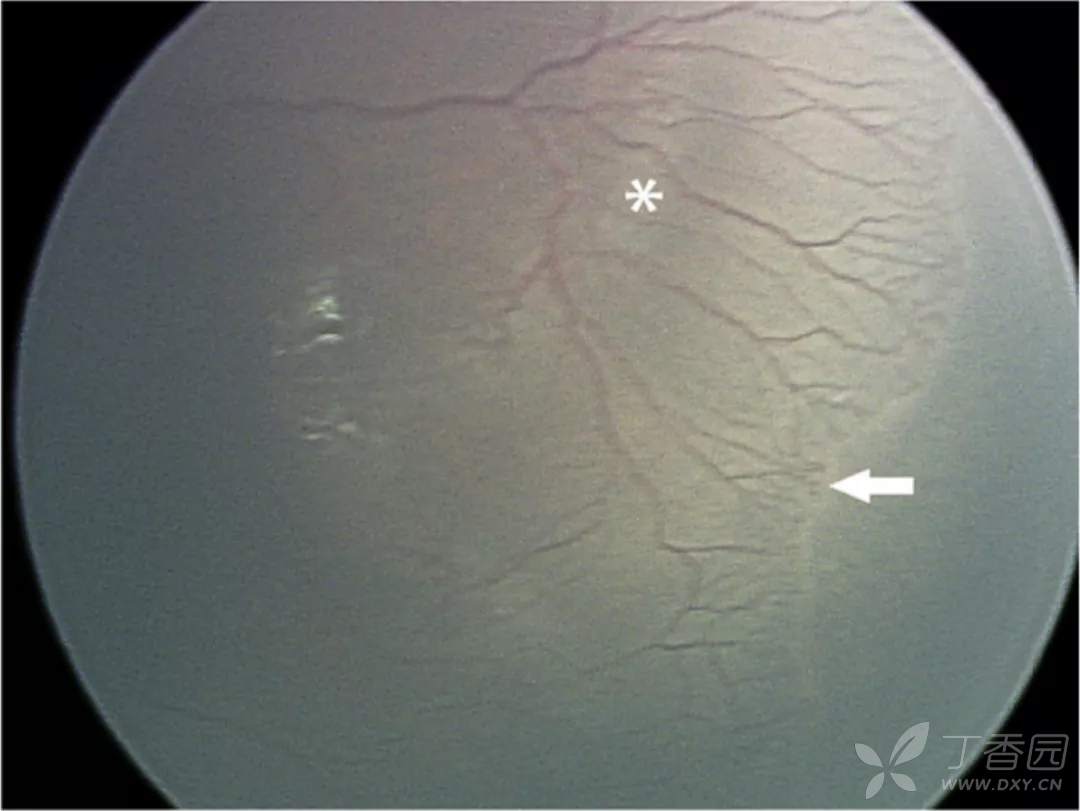

06、急性早产儿视网膜病变4期:部分视网膜脱离

图. 4A期, 视网膜外新生血管牵引可导致视网膜隆起(白点),中心凹(星号)未见脱离,视网膜外新生血管(白箭)可能较脱离区更周边。